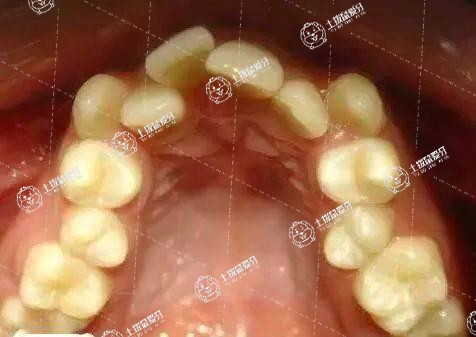

牙齒深覆合通常是指牙齒和牙齒之間的距離過大,使得牙齒參差不齊。時(shí)間長了牙縫之間清洗不徹底就會(huì)滋生大量細(xì)菌,引發(fā)各種口腔問題,如牙周炎,牙結(jié)石等。與此同時(shí),也會(huì)直接影響到患者面部的美觀。當(dāng)然,牙齒深合也有先天性的,大多成年以后會(huì)自動(dòng)矯正過來。但有些牙齒深覆合是必須要做矯正的。

牙齒深覆合需要矯正,可以改變牙齒經(jīng)常發(fā)生磨損和磨耗的情況,改善面的美觀。牙齒的深覆合即患者的上頜牙咬合,超過下頜牙的1/3,是錯(cuò)頜畸形中的一類。這時(shí)患者的咀嚼力會(huì)降低,牙齒會(huì)經(jīng)常發(fā)生磨損和磨耗;還有患者咬的過緊的時(shí)候會(huì)對關(guān)節(jié)造成很大的壓力,咀嚼力低同時(shí)也會(huì)加重胃腸道負(fù)擔(dān),所以牙齒深覆合是需要矯正的。在矯正的時(shí)候可以定期到醫(yī)院復(fù)查,而且不能吃太多堅(jiān)硬的食物,前期以流食為主。

深覆合就是我們在緊咬牙狀態(tài)下前面的門牙并不是牙尖相對的,而是上面的門牙蓋住下面的門牙一些,那么應(yīng)該蓋住多少呢,一般來說,下牙的三分之一左右被蓋住是比較正常的。當(dāng)然了牙齒如果超過三分之一以上的患者就被稱做深覆合。深覆合有很多的潛在危害,會(huì)影響前牙的切導(dǎo)斜度,日久天長會(huì)對顳下頜關(guān)節(jié)形成創(chuàng)傷,產(chǎn)生疼痛、彈響等等癥狀了。要注意的就是深覆合最大的危害是對顳下頜關(guān)節(jié)的損傷,尤其是閉鎖性深覆合是顳下頜關(guān)節(jié)紊亂綜合癥的常見錯(cuò)合。此類人群下頜處于遠(yuǎn)中位置,下頜前伸運(yùn)動(dòng)嚴(yán)重障礙,因此是需要進(jìn)行矯正的。